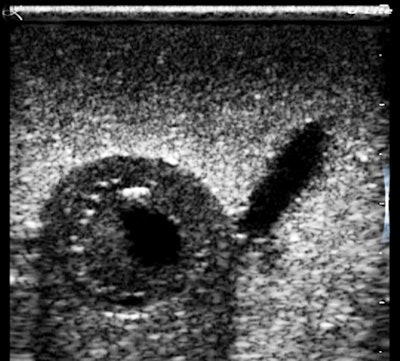

Look at the magnified cherry images below. They hold together beautifully, and there is an impressive visible grayscale intensity range. The fluid cleft and the pitted center of the cherry have sharp clear boundaries, and there is an acoustic shadow effect deep to the cherry. These settings were mainly for contrast resolution, which is the most important performance factor for recognizing and excluding pathology. I could have done better with near-field gain and I fixed that later.